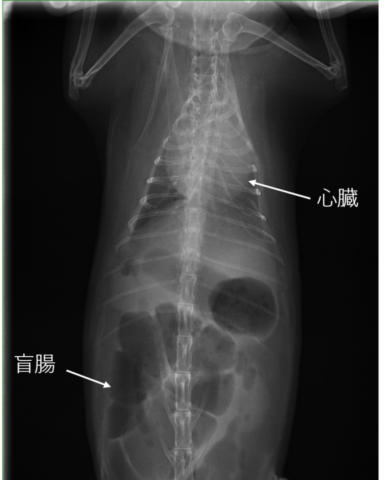

レントゲンを撮ったところ、急性胃拡張で胃にガスがパンパンに溜まっているとのこと。非常に危険な状態なので、麻酔をかけてガスを抜く処置をするため、そのまま入院が決まりました。

その場で検査していただいたところ、体重は更に減って1kgを下回っていたことに加え

①低体温35.4℃(正常な直腸温は38.℃~39.5℃)

②鼓腸症

③心臓肥大

と、大きく3つも悪いところがあり、危険な状態で、このまま急変もあり得るとの診断でした。

ずっとぎゅるぎゅる鳴り続けていたお腹は、うっ滞だけでなく鼓腸症という病気でガスが腸にパンパンに溜まっていることがわかりました。

この日、心臓肥大の原因を特定するためのエコー検査を行っていただきました。

心臓に水(心嚢水)が溜まり、加えて肺にも水(胸水)が溜まっているため呼吸が苦しい状態であるとの説明を受けました